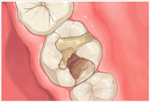

アメリカのヒューストン発のDoc's Best Cements(ドックベストセメントまたはドックスベストセメント)により痛くない、削らない、神経を取らない治療が可能になりました。(従来の保険治療で行うような予防的な拡大処置としてむし歯以外の健全な歯質を削らないということです。

まったく歯を削らないという意味ではありません。) ドックベストセメントは、Dr.Fraserが1990年に開発したミネラルを含んだ銅セメントです。

ドッグベストセメント治療は、銅、酸化亜鉛、酸化チタン、リン酸、水酸化アルミなどを主成分とする素材を使います。鉄(Fe)イオンと銅(Cu)イオンのコンビネーションによる殺菌力が、むし歯に効果的に作用することで、むし歯菌に侵された歯の象牙質の無菌化を促すという大きな働きがあります。

メリット一般的なむし歯治療と違い、ドッグベストセメント治療は必要以上に歯を削らないで済みますので、歯を削る違和感もなく、痛みを感じないので、麻酔注射も必要ない場合がほとんどです。

ドッグベストセメントの鉄(Fe)イオンと銅(Cu)イオンのコンビネーションによる殺菌力で患部を殺菌することで、神経を残せる可能性が高くなります。

むし歯菌に侵されている歯の内部の象牙質をドッグベストセメントの鉄(Fe)イオンと銅(Cu)イオンで殺菌することで、歯の象牙質部分の再石灰化を促します。